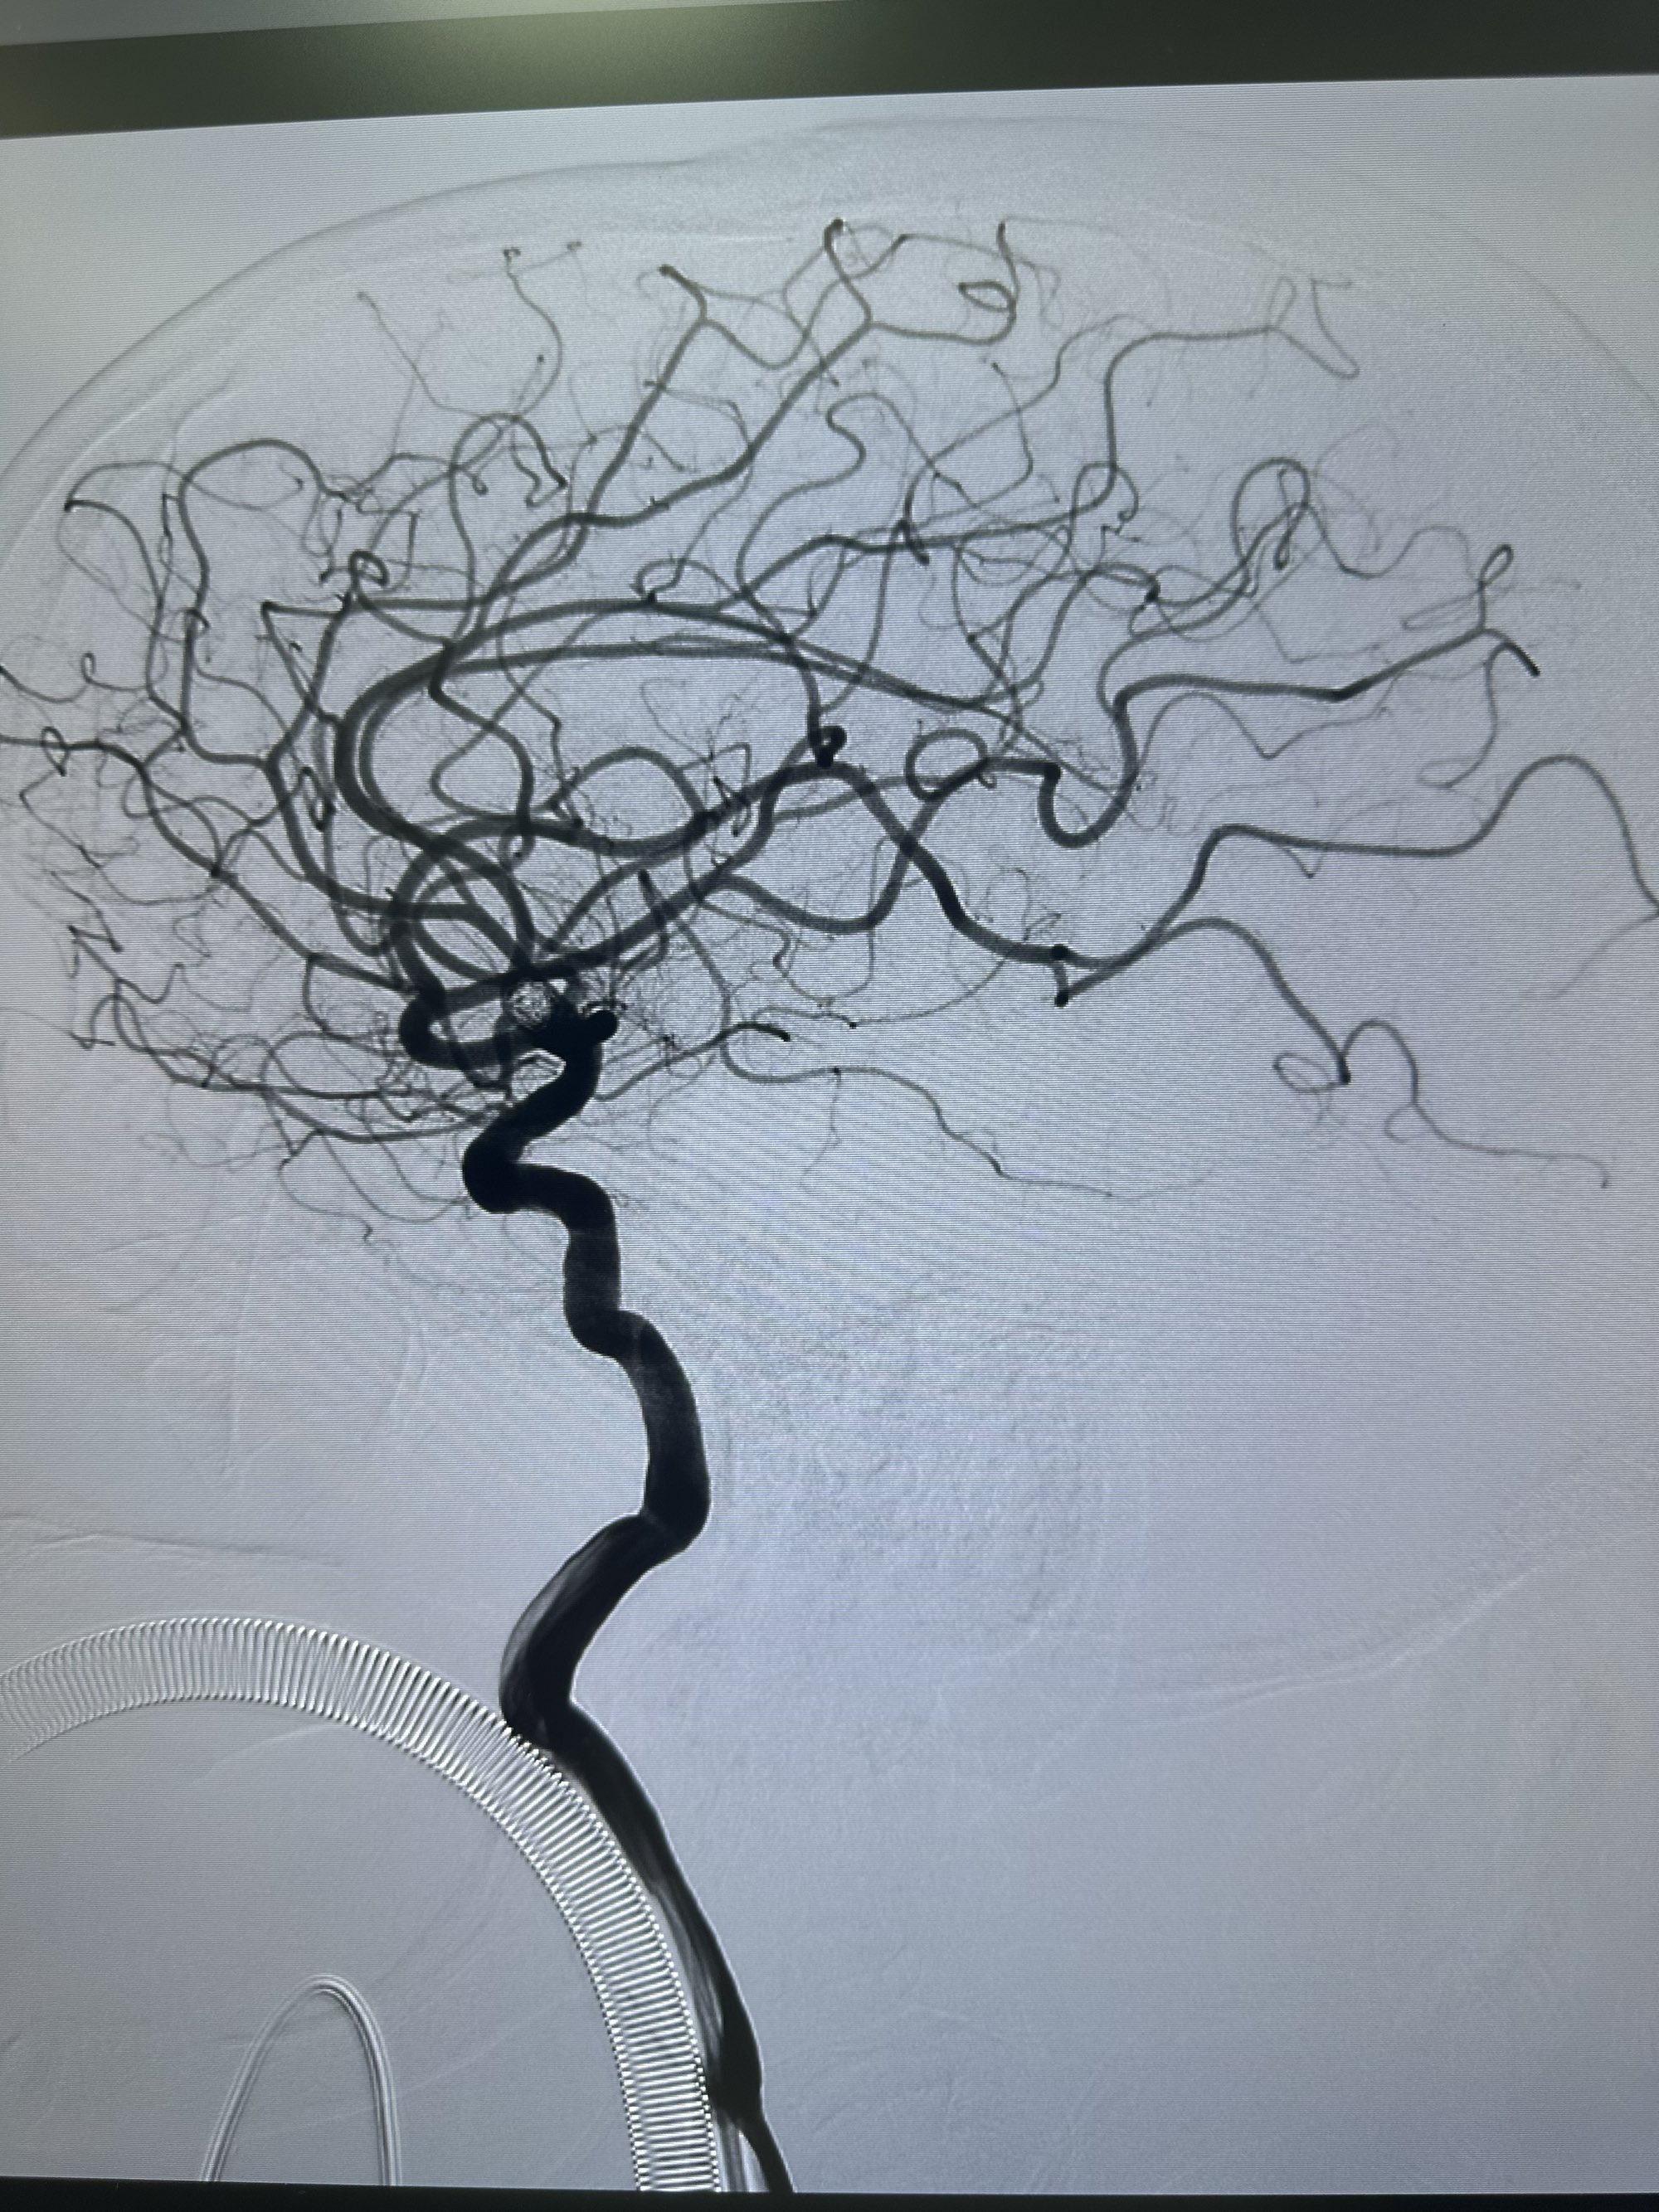

第一枚圈选择4*8的target 3D

圈的形态